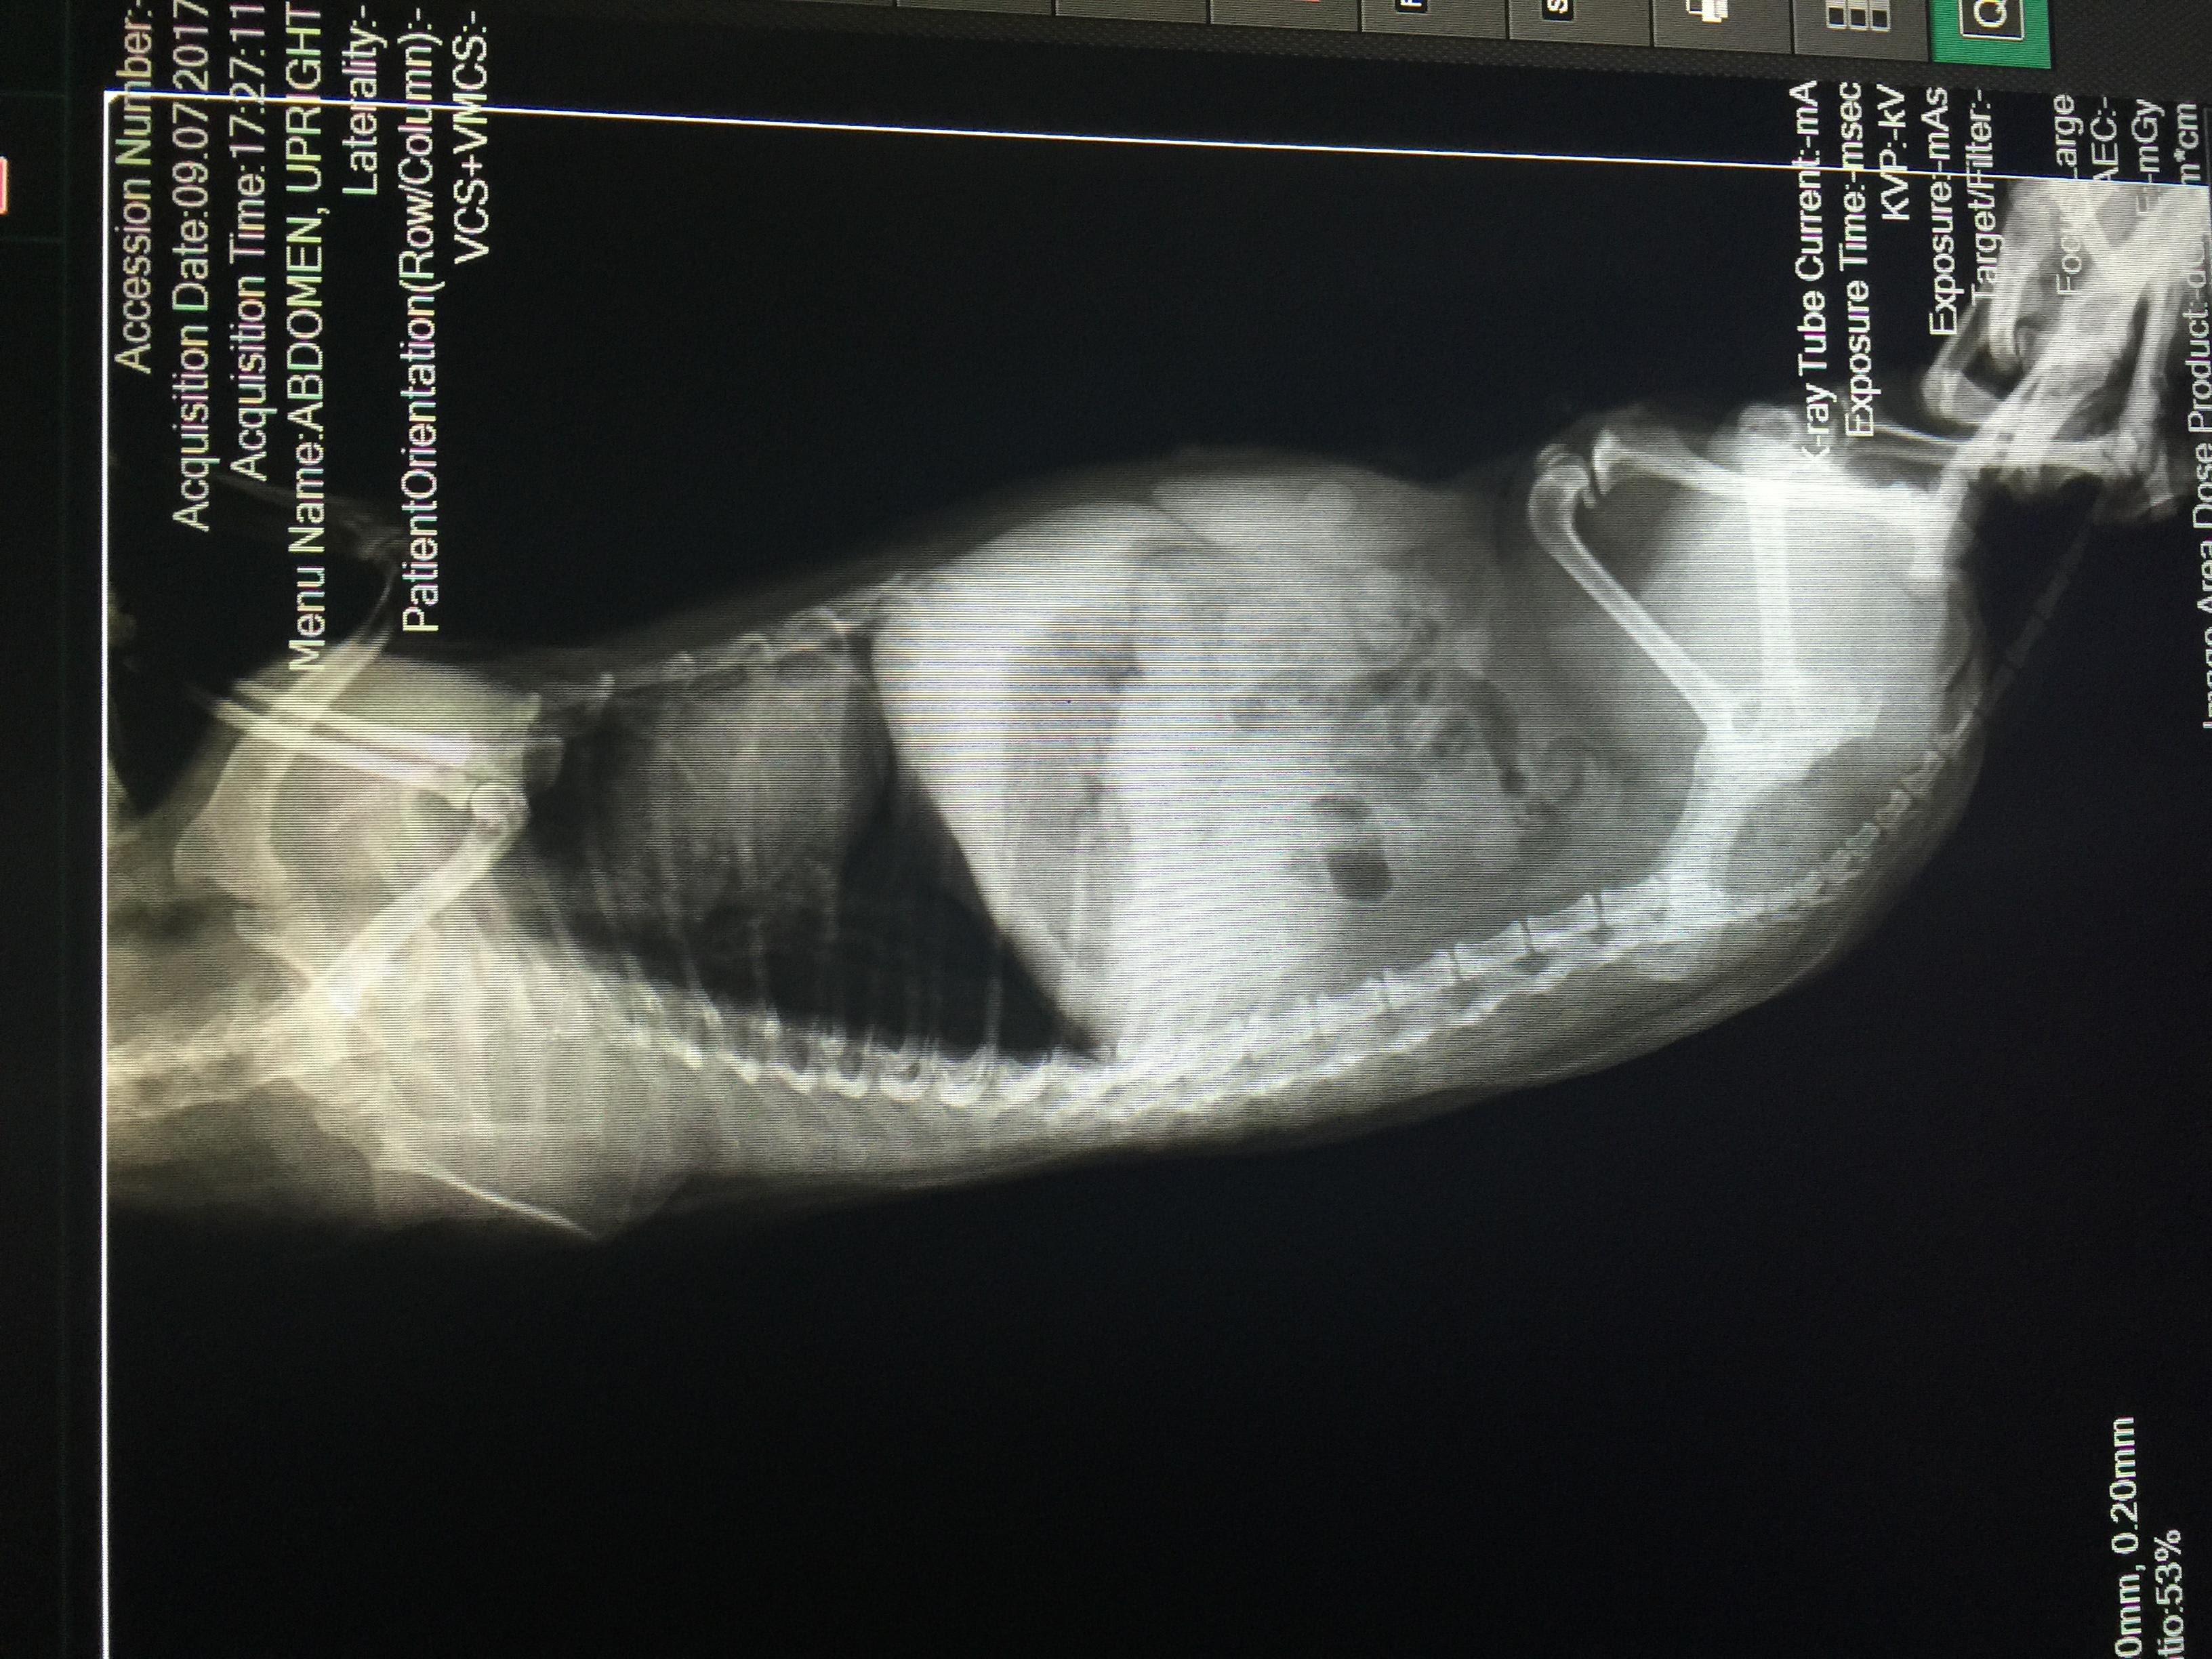

First of, thanks so much to Dr. Roca for the detailed response on my first post! I didnt include my dog's xray pics (taken today) so i'm attaching it here. Still waiting to hear back from my vet but would like to know if there are any red flags or possible issues i should discuss with her. Maicah is 10-12yo, shipoo mix, currently on ehrlichia meds: doxy and prednisone. Her gait is a bit stiff and i saw slight signs of discomfort when i massage her back. Any info will be much appreciated!

The x-rays are a bit difficult to interpret because they are a little fuzzy, but I can see that Maicah has some minor changes on the bottoms of her vertebrae - called spondylosis. This can definitely cause discomfort in the back. I would talk to her vet about treatments that can help with this kind of pain. I am not able to evaluate her hind limbs because the assistant's hands are covering them up. Another possible cause of her stiffness is joint pain caused by the ehrlichia infection. This should improve with appropriate treatment.